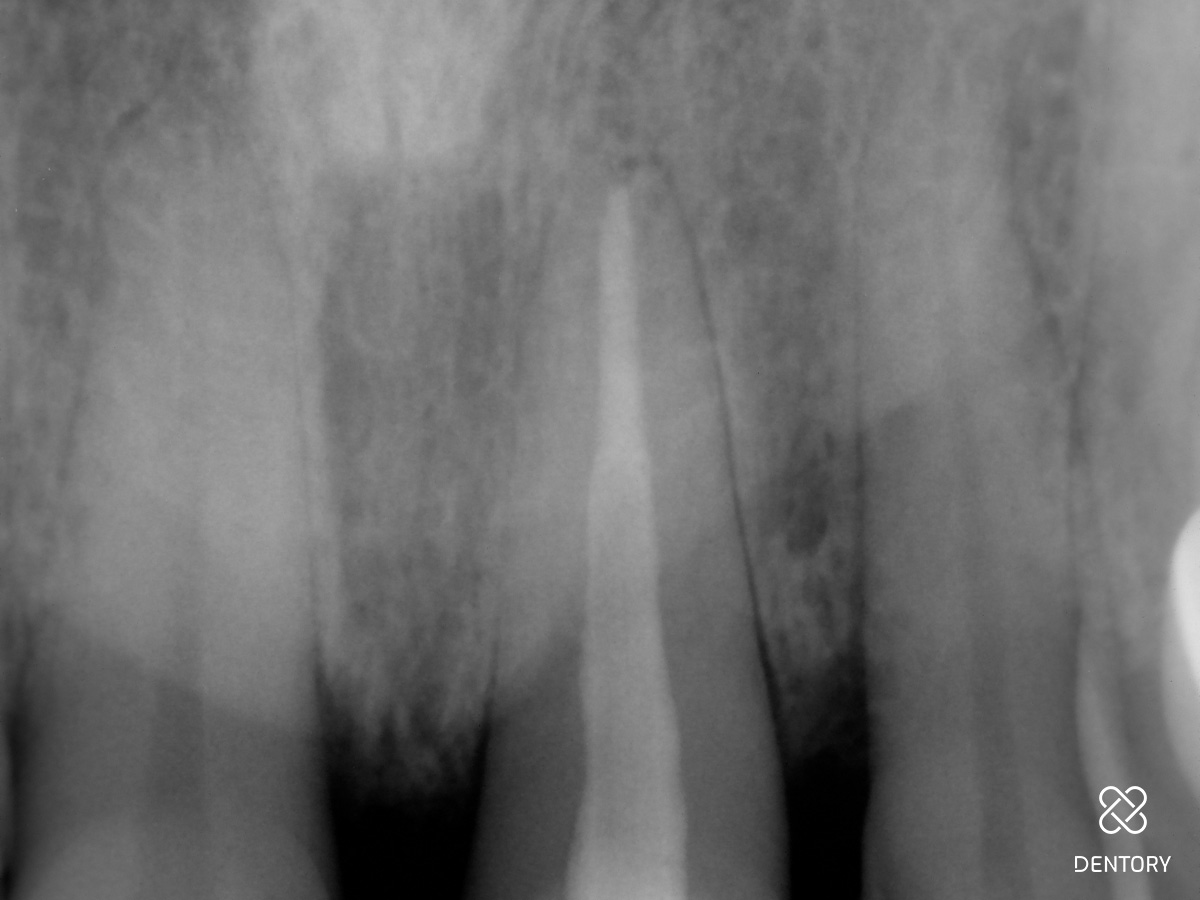

Abbildung 14

Röntgenkontrolle: Kontrolle der Füllung mit MTA-Plug.